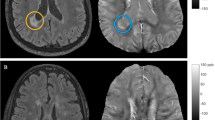

He attended the clinic for routine checkups. Two and a half years after his initial injury, he appeared at the SCI clinic complaining of having suffered paresthesias for 2 months, beginning in his left hand and progressing to his right shoulder, arm and hand. He also had difficulty with fine movements of the first and second finger of the right hand. At that time we were concerned about the possibility of post-traumatic syringomyelia and an magnetic resonance imaging (MRI) of his cervical and dorsal spine was arranged. The MRI revealed no signs of syringomyelia but identified demyelinating areas at the cervical level of the spinal cord. A contrast study was then completed that revealed three instances of demyelinating focus between C1 and C6 and one area of active inflammation at C2–C3 (Figure 2). A brain MRI revealed multiple demyelinating lesions, some of which are enhanced by Gadolinium, suggestive of MS (Figure 3). A lumbar puncture was performed, demonstrating the presence of oligoclonal bands in the cerebrospinal fluid. The diagnosis of MS was confirmed by a neurologist and treatment was started with glatiramer acetate administered daily. The initial symptoms disappeared and only a light paresthesia in the right hand persisted. Two years later he has no new symptoms and continues with the same medication and good tolerance. The patient is currently still independent in transfers, activities of daily living and wheelchair management.